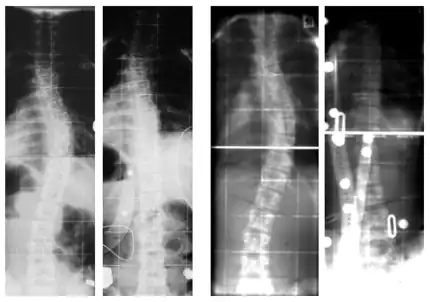

Unterschiedliche Skoliosemuster: alles Skoliosen mit einer Stärke von 40° Cobb

Eine Skoliose (altgriechisch σκολίωσις skolíōsis, deutsch ‚Krümmung‘) ist als asymmetrische Fehlbildung eine Seitabweichung der Wirbelsäule von der Längsachse mit Rotation (Verdrehung) der Wirbel um die Längsachse und Torsion der Wirbelkörper – begleitet von strukturellen Verformungen der Wirbelkörper. Diese Form der Rückgratverkrümmung kann nicht mehr durch Einsatz der Muskulatur aufgerichtet werden. Die Wirbelsäule bildet dabei in der Regel mehrere, einander gegenläufige Bögen, die einander kompensieren, um das Körpergleichgewicht aufrechtzuerhalten (S-Form). Der Cobb-Winkel (nach John Robert Cobb) dient als Maß für die Beurteilung der Skoliose.